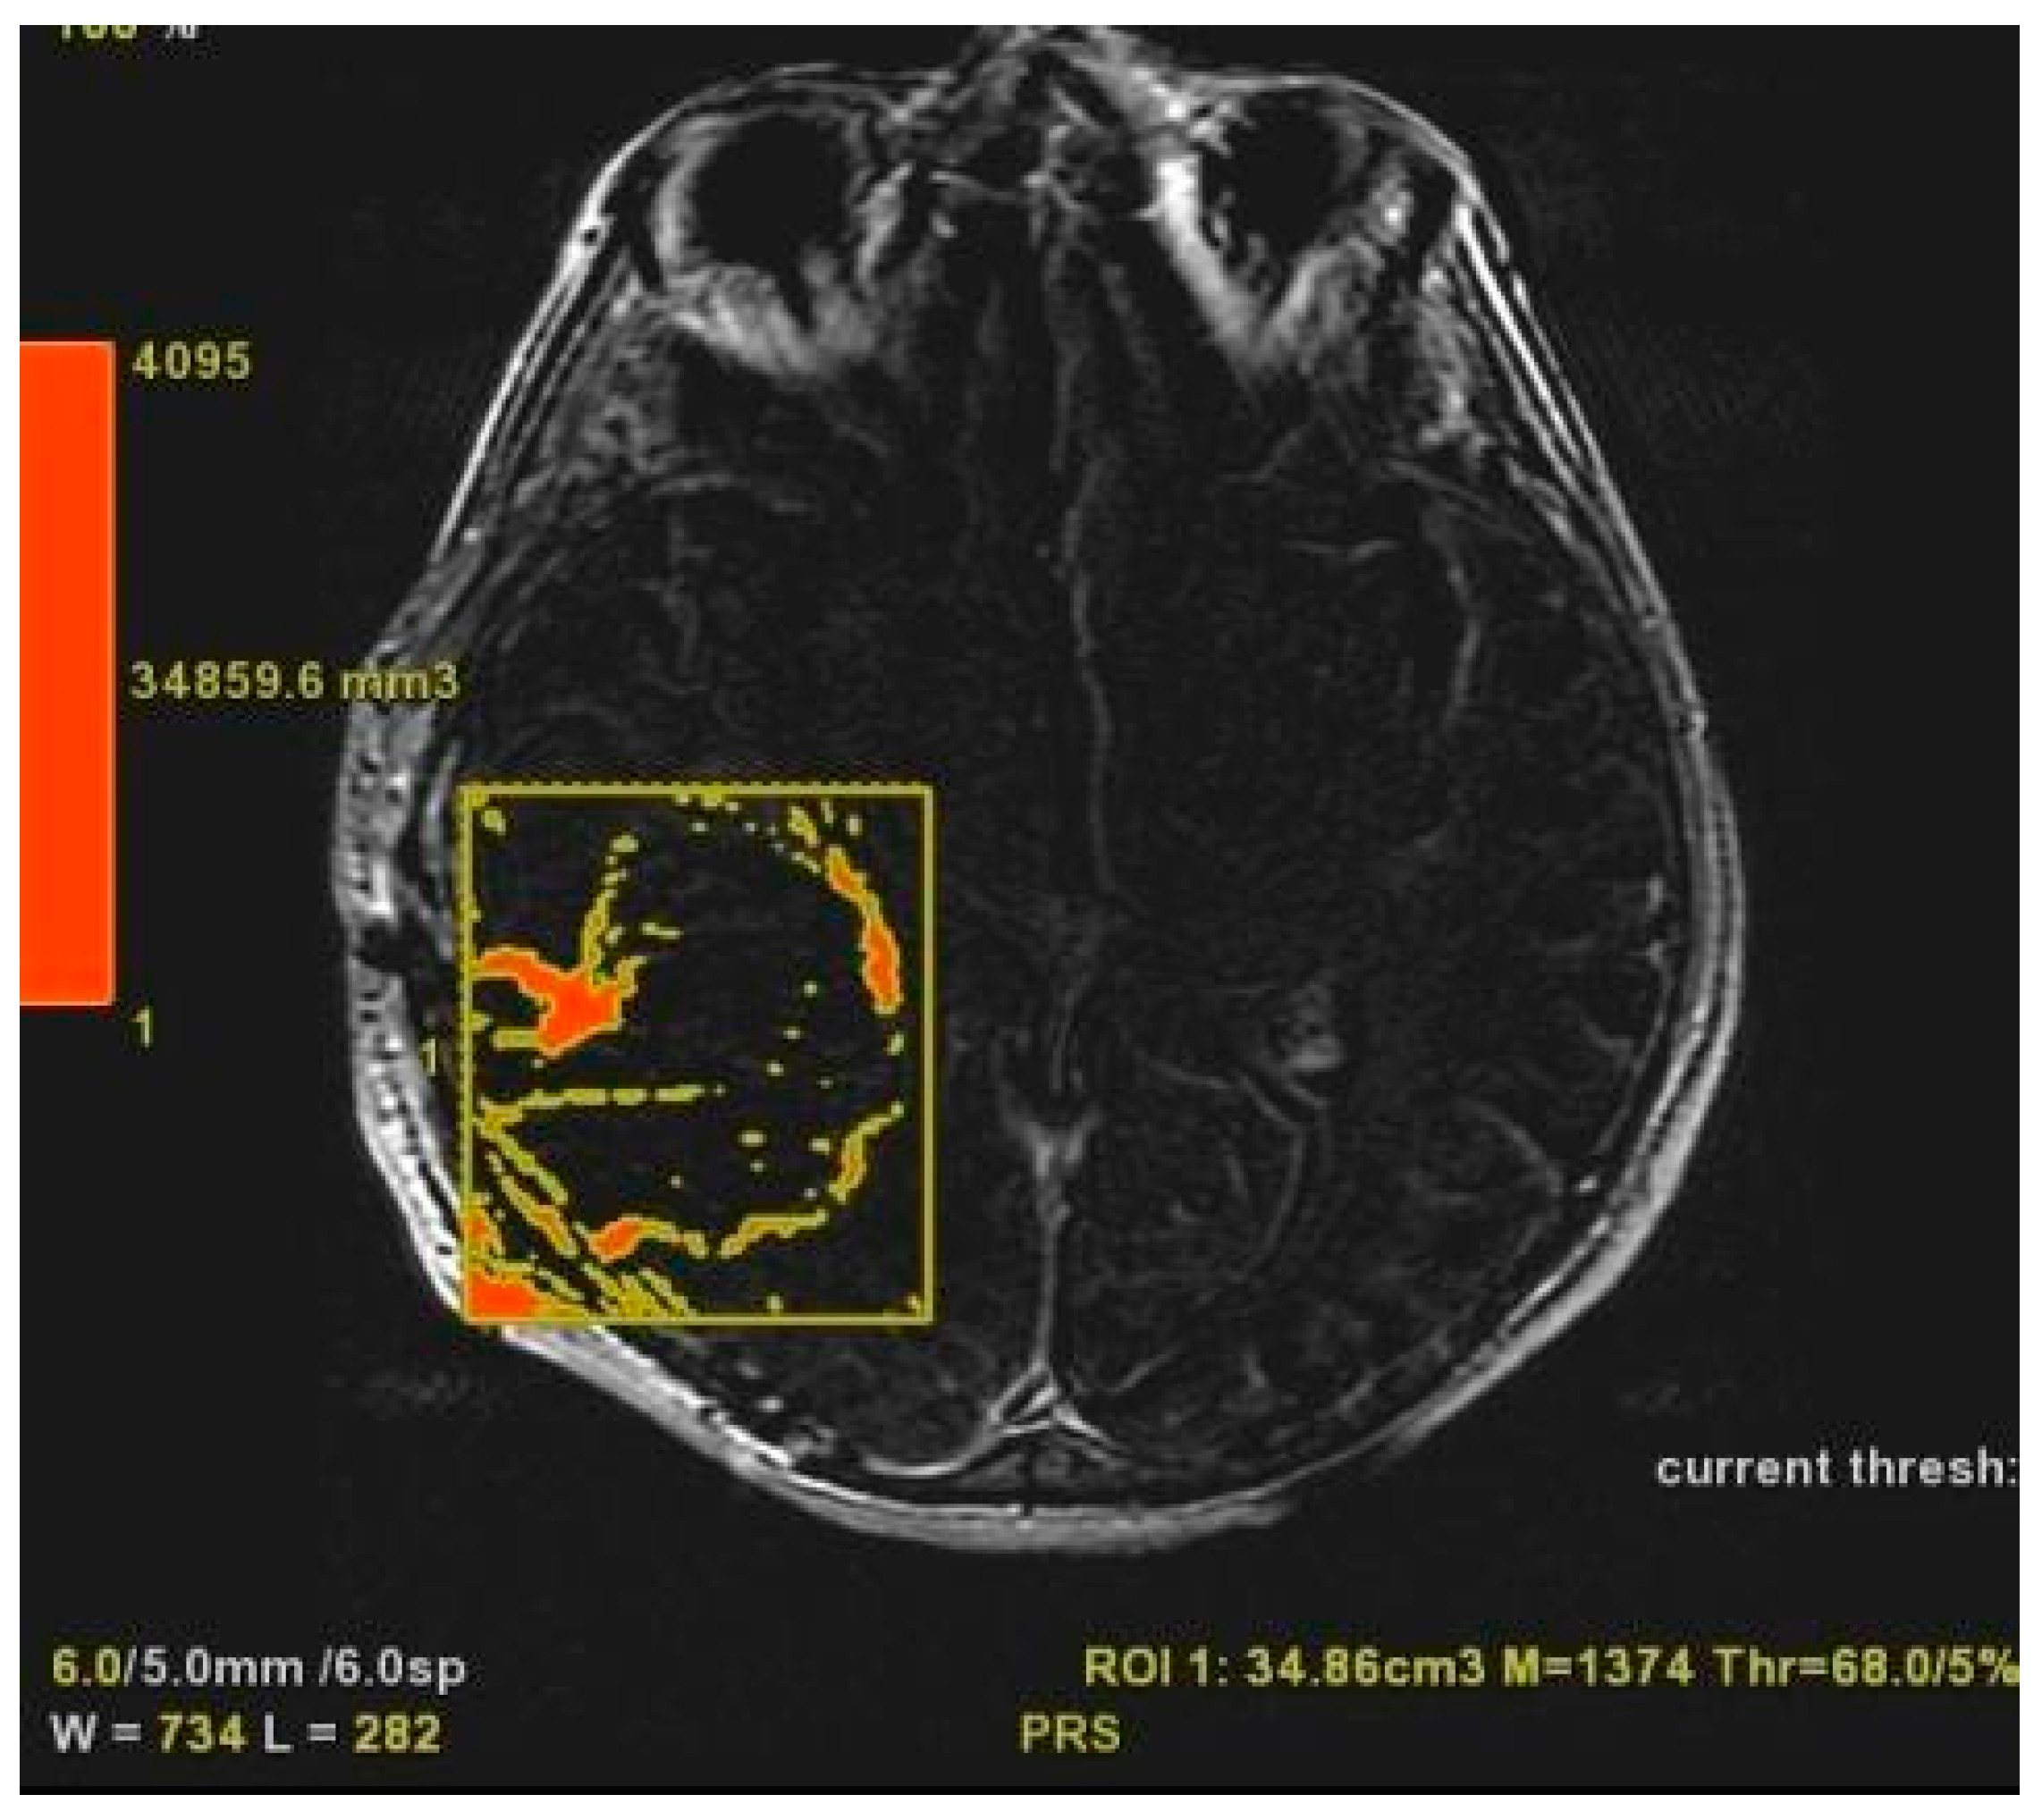

CE-PTV was evaluated on 2D axial Contrast Enhanced T1 weighted (CE-T1w) images (slice thickness: 5 mm.; slice spacing: 5,5-6 mm.), by contouring manually enhanced tumor areas on every single axial slice, excluding necrosis; the same analysis was subsequently performed with semi-automatic method by using the apposite tool of the AW server 3.2 [Figure 1 and Figure 2].

Figure 2. CE-PTV semi-automatic evaluation.

Preprints 86216 g002